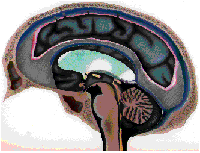

Syndrom Arnolda Chiari lub po prostu Chiari został opisany ok 100 lat temu i wskazuje na istnienie przepukliny w wewnętrznej części mózgu: migdałki móżdżku lub migdałki razem z dolną częścią móżdżku przechodzą przez otwór wielki podstawy czaszki w kierunku kanału kręgowego. W przypadku Syndromu Arnolda Chiari II lub III tę sytuację tłumaczy pociąganie od dołu i napięcie rdzenia kręgowego wywołane przez jego zakotwiczenie (rozszczep kręgosłupa lub przepuklinę oponowo-rdzeniową). W przypadku Syndromu Arnolda Chiari I, w czasie gdy dokonywano klasyfikacji, nie zaobserwowano żadnej dodatkowej malformacji, która tłumaczyłaby ten proces chorobowy. Proponowano różne wyjaśnienia, np. zaburzenia w krążeniu płynu mózgowo rdzeniowego lub zmniejszenie pojemności czaszki w rejonie potylicznym, w którym znajduje się móżdżek.

Żeby uniknąć napięcia w rdzeniu kręgowym, dolna część mózgu nazywana migdałkami możdżku, obsuwa się przez otwór potyliczny, który łączy czaszkę z kręgosłupem, powodując syndrom Arnold-Chiari, chorobę opisaną ponad 100 lat temu i o niewiadomej przyczynie. Przecięcie filum terminale w przypadku syndromu Arnold-Chiari, powoduje że napięcie i obsuwanie się migdałków móżdżku znika i zatrzymuje ich zaciskanie się w otworze potylicznym. Operacja powoduje że wiele z objawów znika, jednak migdałki nie przemieszczają się ku górze ze względu na ich słabą elastyczność.

Napięcie rdzenia kręgowego oprócz tego że powoduje siringomielię, powoduje również skoliozę. Żeby uniknąć napięcia w rdzeniu, zewnętrzne części mózgu czyli migdałki móżdżku, schodzą w dół przez otwór potyliczny, któty łączy czaszkę z kręgosłupem, powodując malformację Arnolda Chiari, chorobę opisaną ponad 100 lat temu, której przyczyna jest nieznana.